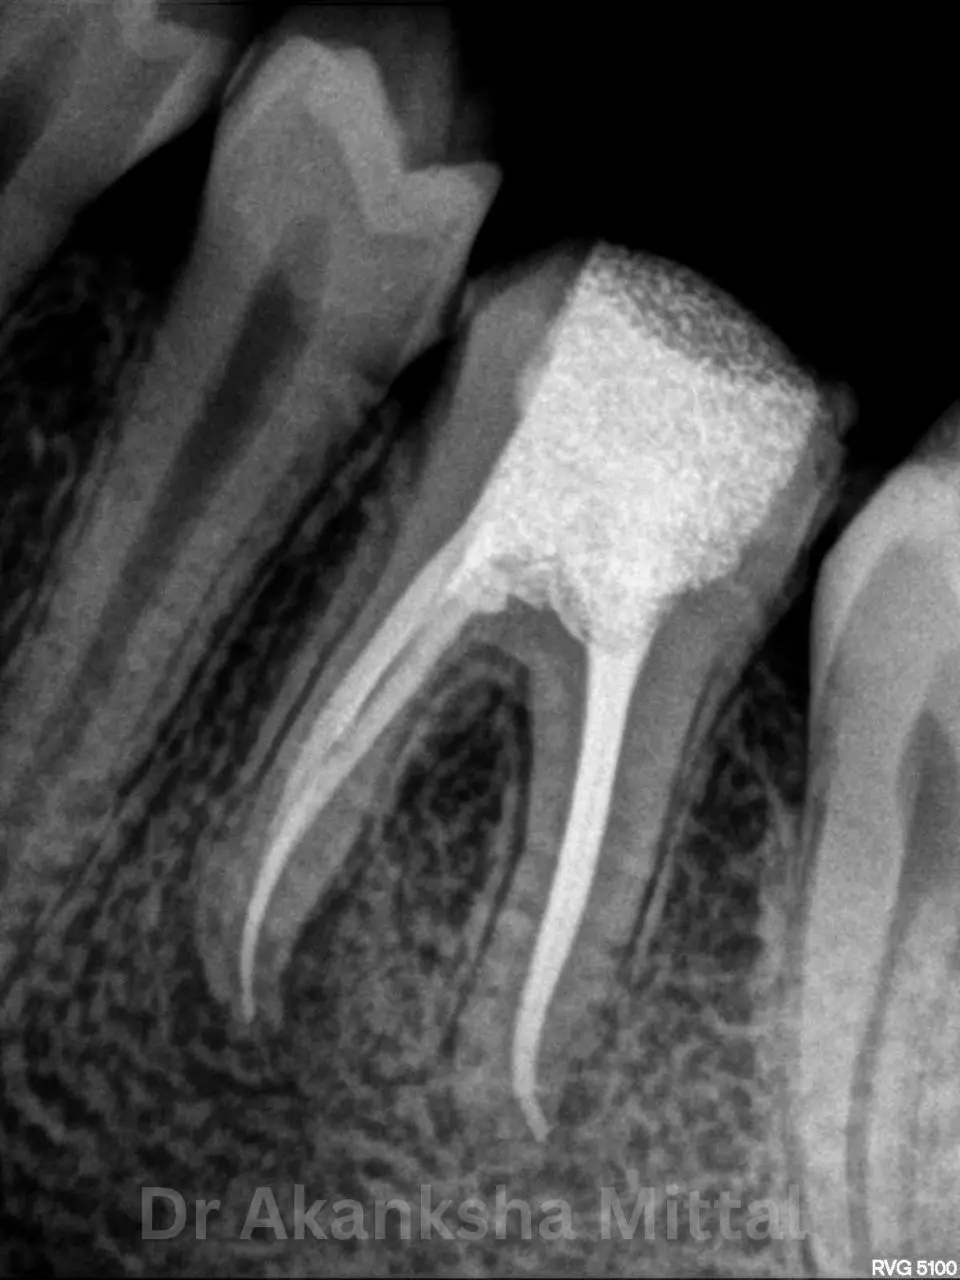

At Teethtime, we specialise in modern root canal treatment designed to eliminate tooth pain and preserve your natural tooth. Under the expert care of Dr Akanksha Mittal (MDS), our clinic uses advanced rotary technology to make your experience gentle and effective.

A root canal is recommended when the inner pulp of the tooth becomes infected due to deep decay, cracks, or injury. If left untreated, the infection can cause severe pain and may lead to tooth loss.

Our goal at Teethtime is to remove the infection and restore your tooth’s strength and function using the most advanced dental technology available in Chandigarh.